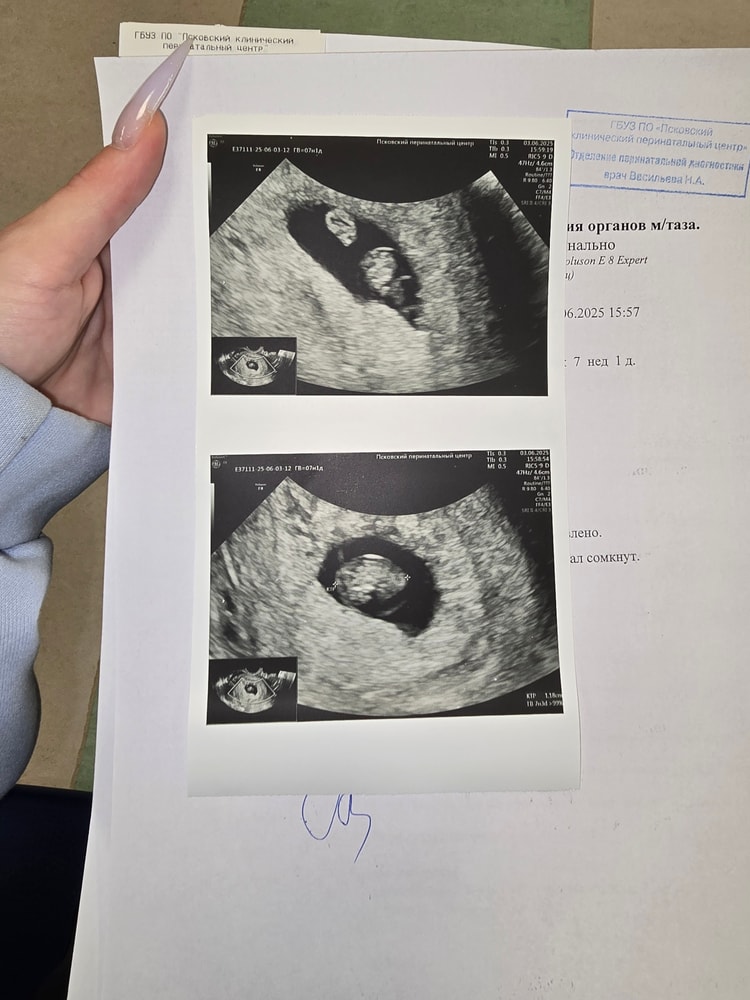

У меня срок по акушерскому 7 недель 1 день а по узи 7 недель и 3 дня

Это нормально?